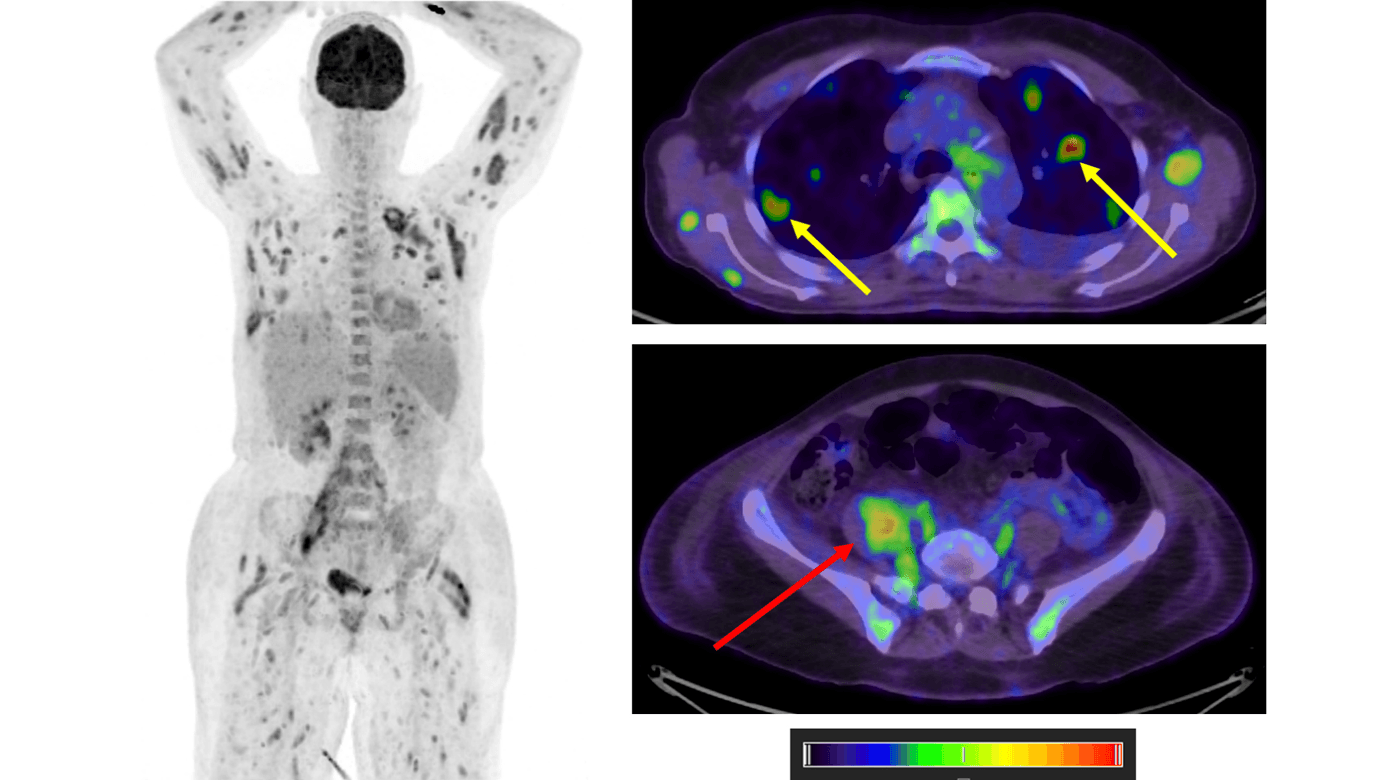

18F-FDG-PET/CT’en viste fordelingen af glukosemetabolisme i kroppen. Skanningen viste øget metabolisme i vertebra L4 og i højre m. psoas major. Herudover sås spredte hypermetaboliske foci i muskulaturen og i bilaterale abscederende lungeinfiltrater. Endvidere var der diffust øget metabolisme i rød knoglemarv og en forstørret milt. Fundene var forenelige med spondylitis ledsaget af psoas major-absces (se rød pil), udbredte septiske embolier i muskulatur og lunger (se gule pile) samt aktiveret rød knoglemarv. Differentialdiagnostisk kan PET-skanningen give mistanke om dissemineret malign sygdom og polymyositis [2].